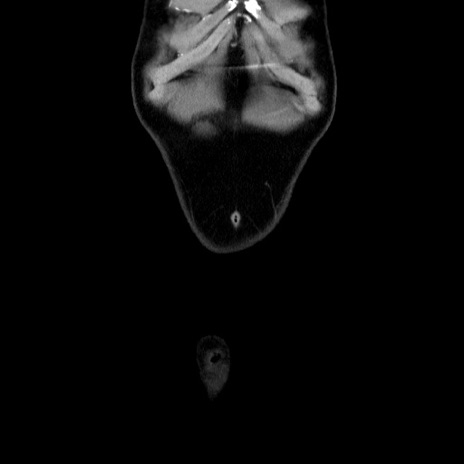

横断像

矢状断像